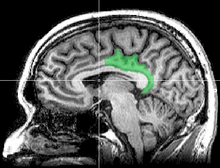

![]() Medial surface of left cerebral hemisphere. | |

The posterior cingulate cortex (PCC) is the backmost part of the cingulate cortex, lying behind the anterior cingulate cortex. This is the upper part of the "limbic lobe". The cingulate cortex is made up of an area around the midline of the brain. Surrounding areas include the retrosplenial cortex and the precuneus.

Cytoarchitectonically the posterior cingulate cortex is associated with Brodmann areas 23 and 31.

The posterior cingulate cortex is the backmost part of the cingulate cortex, lying behind the anterior cingulate cortex. The PCC forms a part of the posteromedial cortex, along with the retrosplenial cortex (Brodmann areas 29 and 30) and precuneus (located posterior and superior to the PCC). The PCC, together with the retrosplenial cortex, forms the retrosplenial gyrus. The posterior cingulate cortex is bordered by the following brain regions: the marginal ramus of the cingulate sulcus (superiorly), the corpus callosum (inferiorly), the parieto-occipital sulcus (posteriorly), and Brodmann area 24 (anteriorly).[4]